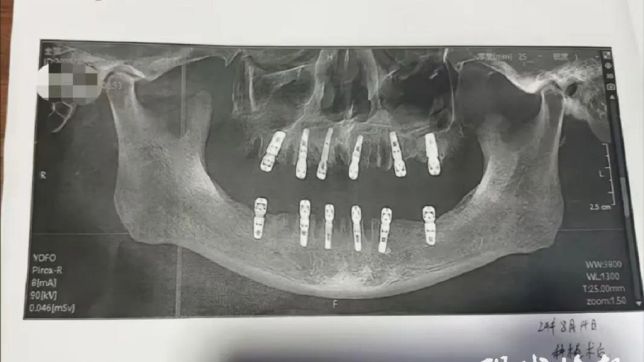

Enquanto muitos jovens sofrem ao tirar os quatro dentes sisos de uma só vez, um chinês acabou morrendo 13 dias após extrair 23 dentes e implantar 12, na mesma cirurgia.

Ele teria assinado um termo de consentimento para a cirurgia de extração de 23 dentes e a colocação imediata de 12 implantes. Depois de concluir o procedimento dentário, Huang teria continuado a sentir dor nos dentes e, no dia 27/8, morreu em decorrência de uma parada cardíaca.

No entanto, de acordo com o formulário de consentimento assinado por Huang e obtido pelo The Paper, durante a cirurgia molares foram implantados no mesmo dia da extração, o que era inconsistente com o que a equipe informou.

Para se ter uma ideia da gravidade do procedimento feito em Huang, normalmente, um adulto tem de 28 a 32 dentes, e o número máximo de dentes que podem ser extraídos de uma vez chega a 10, conforme o site chinês.